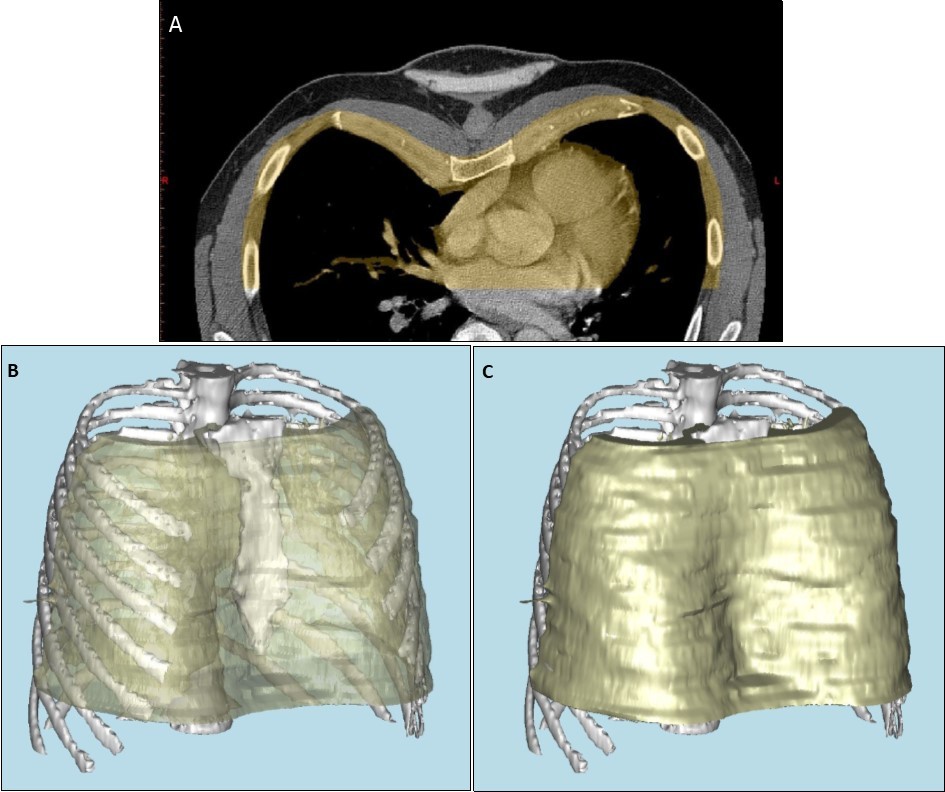

Patients referred for consideration of custom-made chest wall implant underwent an initial consultation with the prosthetists. Three-dimensional computed tomography (3D CT) was performed to assess the skeletal features of the chest wall, using Materialise Mimics software (Materialise, Leuven, Belgium) (Figure 1 a, b, c). A model of the bone structure was then created using a 3D printer, Objet Eden 260vs (Stratasys, Eden Prairie, MN, USA). Alginate was poured onto the 3D model to create an alginate impression (Alginate Colour, DE Healthcare Ltd, Kingthorpe, UK), and a plaster model of the chest wall created from this alginate impression. In lean patients with pectus excavatum, or in Poland syndrome with soft tissue deformity alone, an alginate impression of the whole chest was taken without CT, and the plaster model of the chest created from this. Once a plaster or 3D-printed model was available, a wax prototype of the prosthesis was manually crafted on the plaster model, using carving tools and a blowtorch.

Figure 1.a) Anterior portion of axial computed tomography image of thorax, demonstrating pectus excavatum, with portion used for reconstruction highlighted in yellow. b) and c) three dimensional computer-aided reconstruction of the chest wall model.